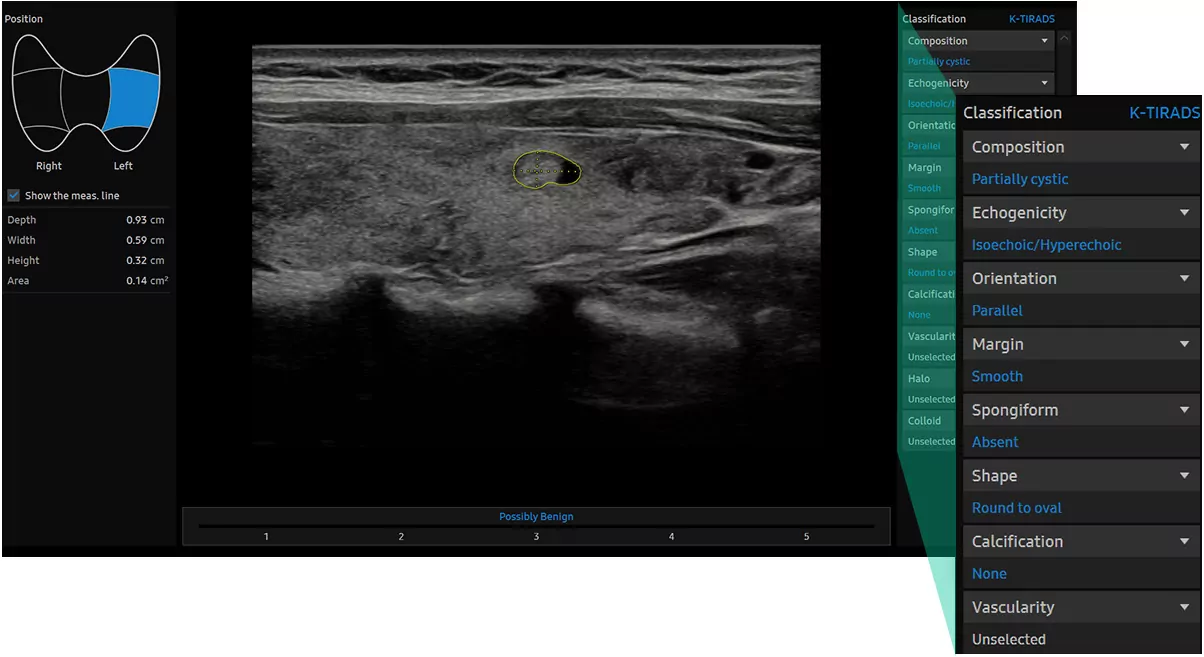

S-Detect™ for Thyroid аналізує вибрані ураження щитовидної залози і показує дані аналізу, надає стандартизовану звітність на основі рекомендацій ATA, BTA, EU-TIRADS і K-TIRADS*; і допомагає в діагностиці завдяки спрощеному робочому процесу.

S-Detect™ for Thyroid